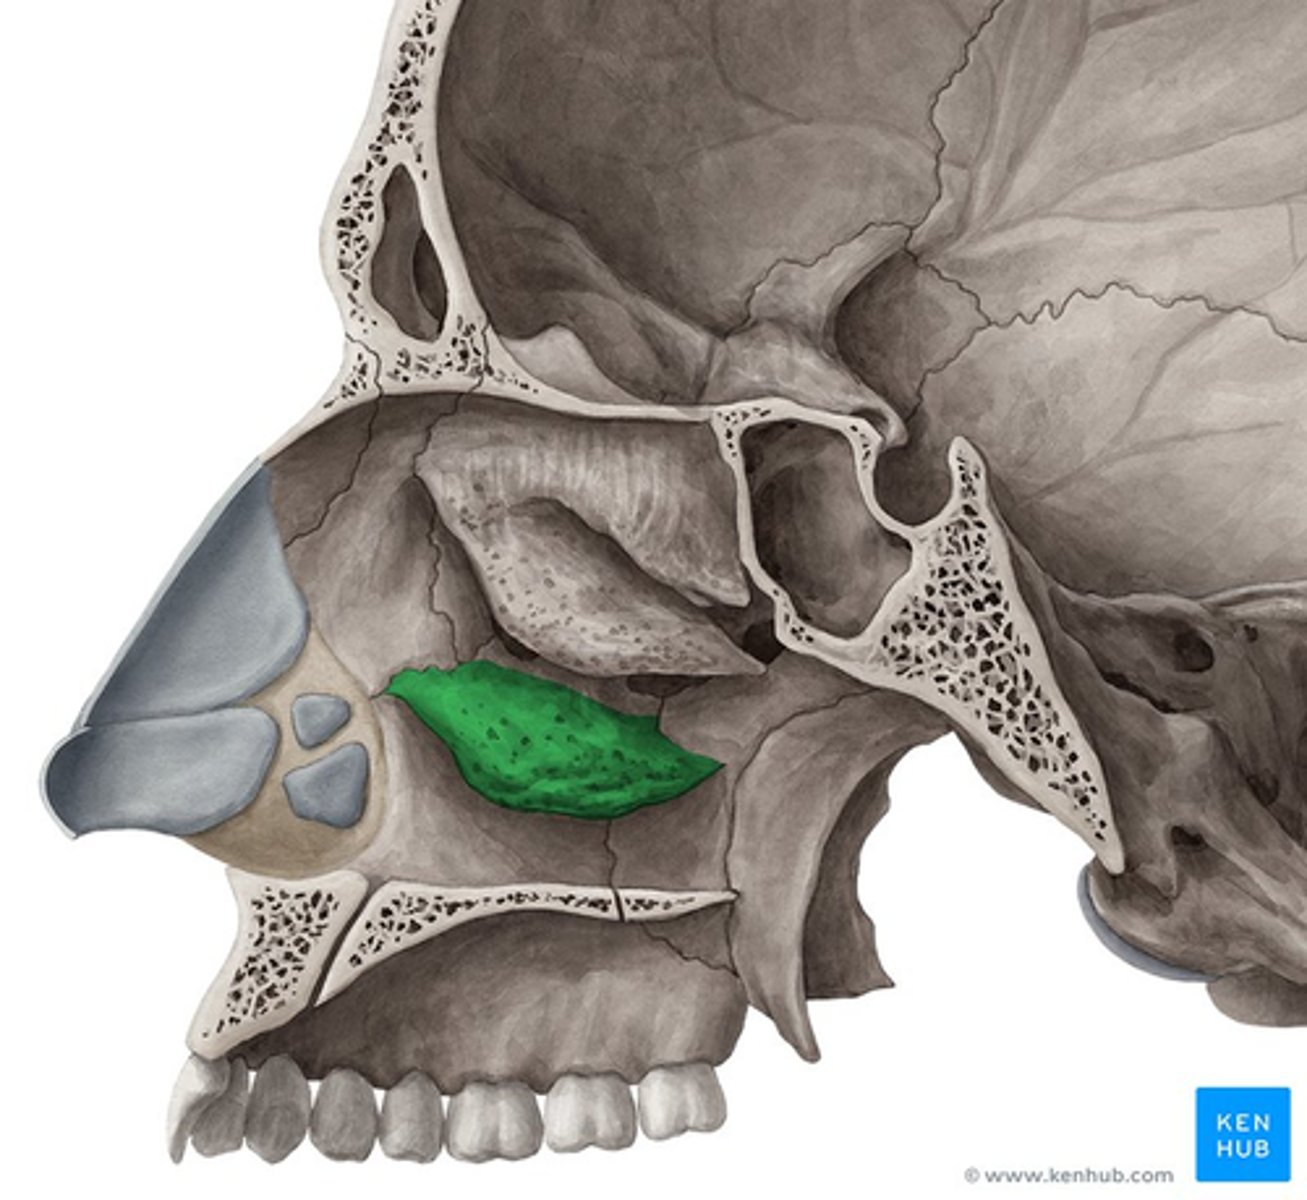

inferior nasal concha

ethmoid bone (perpendicular plate)

palatine bone (horizontal plate)

maxilla (palatine process)